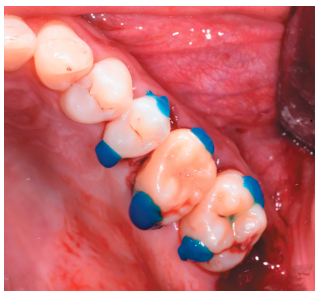

A continuación, se prepararon los dientes 2.5, 2.6 y 2.7 mediante grabado ácido con ácido ortofosfórico al 37% (3M Scotchbond Universal®, Minnesota, EEUU), durante 20 segundos (Figura 11). Tras el lavado abundante con agua de la superfi cie grabada, se aplicó adhesivo de autograbado (3M Scotchbond Universal®, Minnesotta, EEUU), para fi jar el alambre rígido con resina compuesta fluida (Charisma®, Kulzer, Hanau, Alemania) y resina compuesta convencional (G-aenial®, GC, Leuven, Bélgica) (Figura 12).